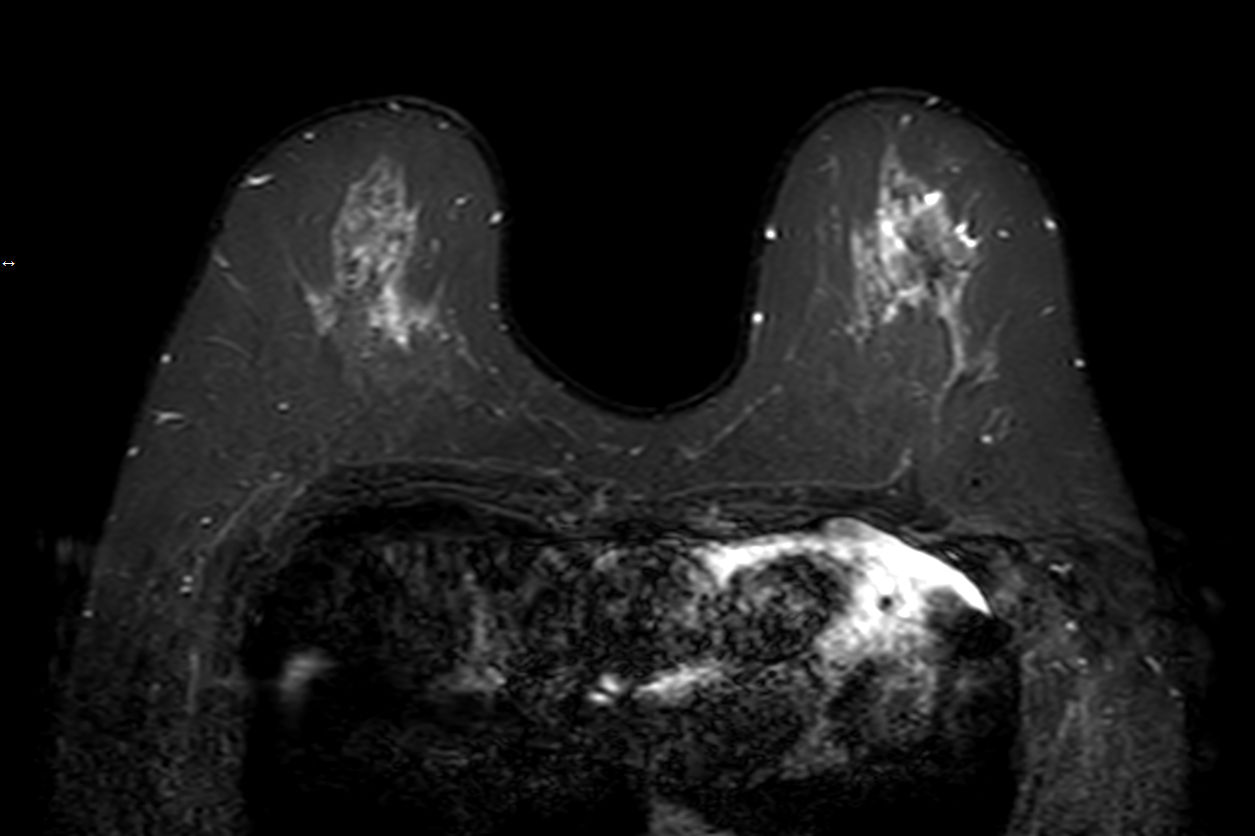

Dynamic 3D mDIXON XD Compressed SENSE

Dynamic 3D mDIXON XD - Post processing Compressed SENSE